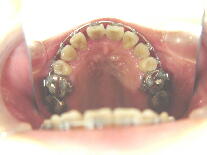

症例2 (20代 女性) 非抜歯例 ![]() ![]() ![]()

初診から6ヶ月後